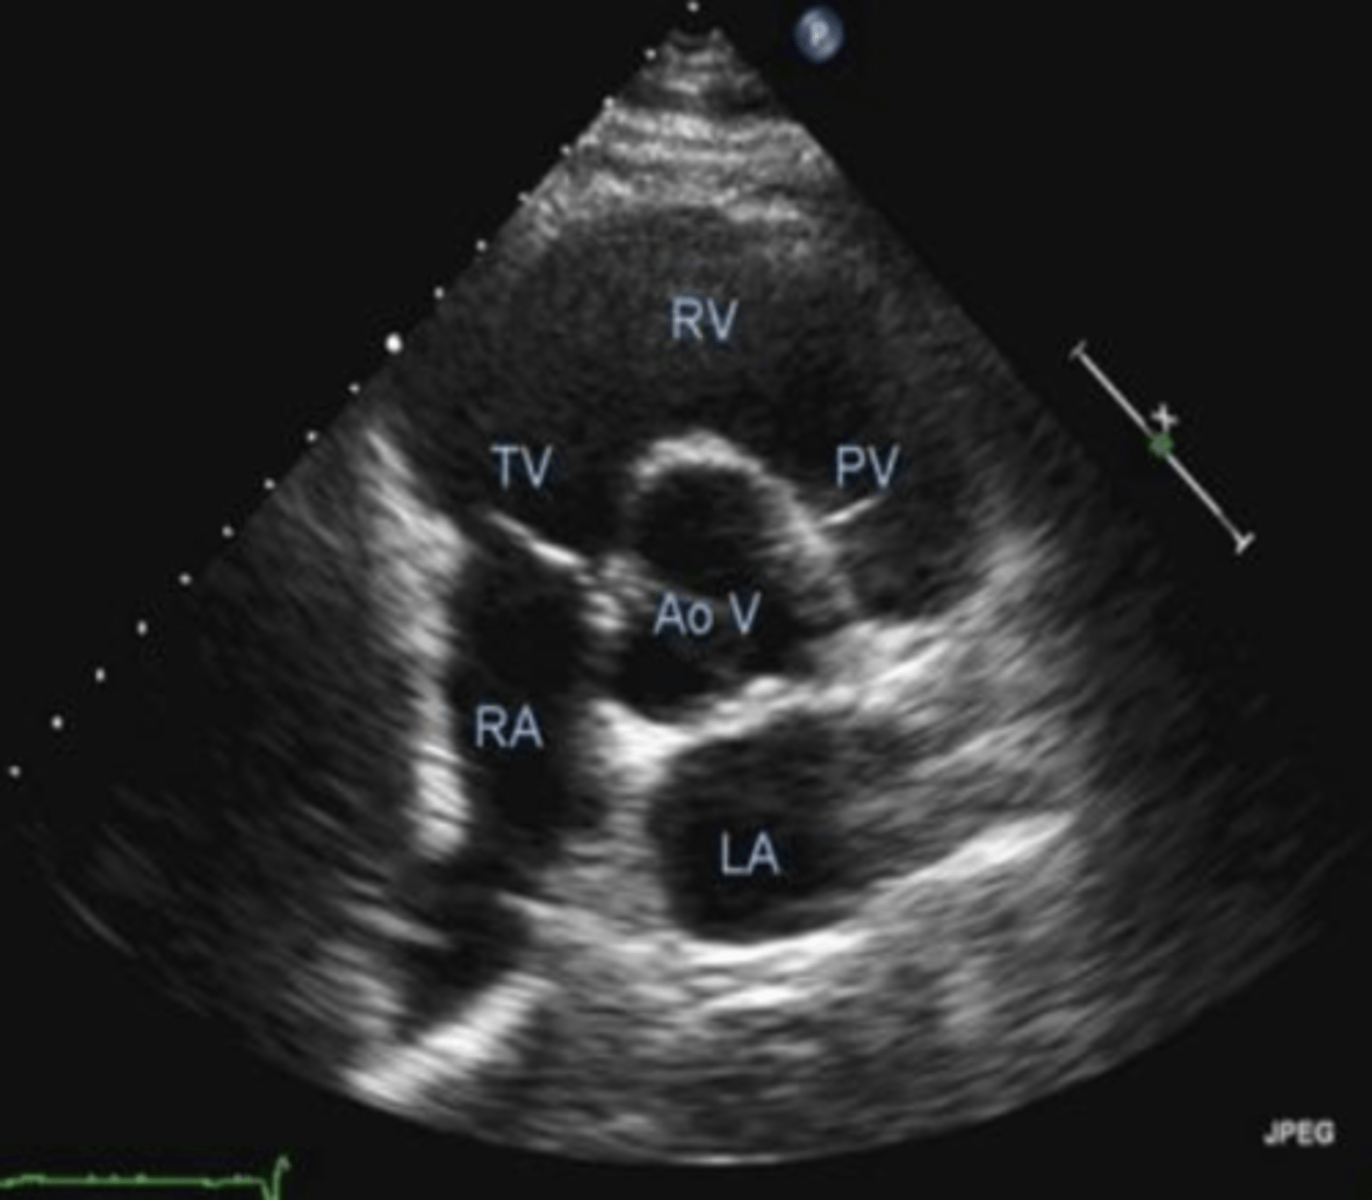

PSSA AoV is used to visualize _____, ____, and ___

TV, PV, AoV